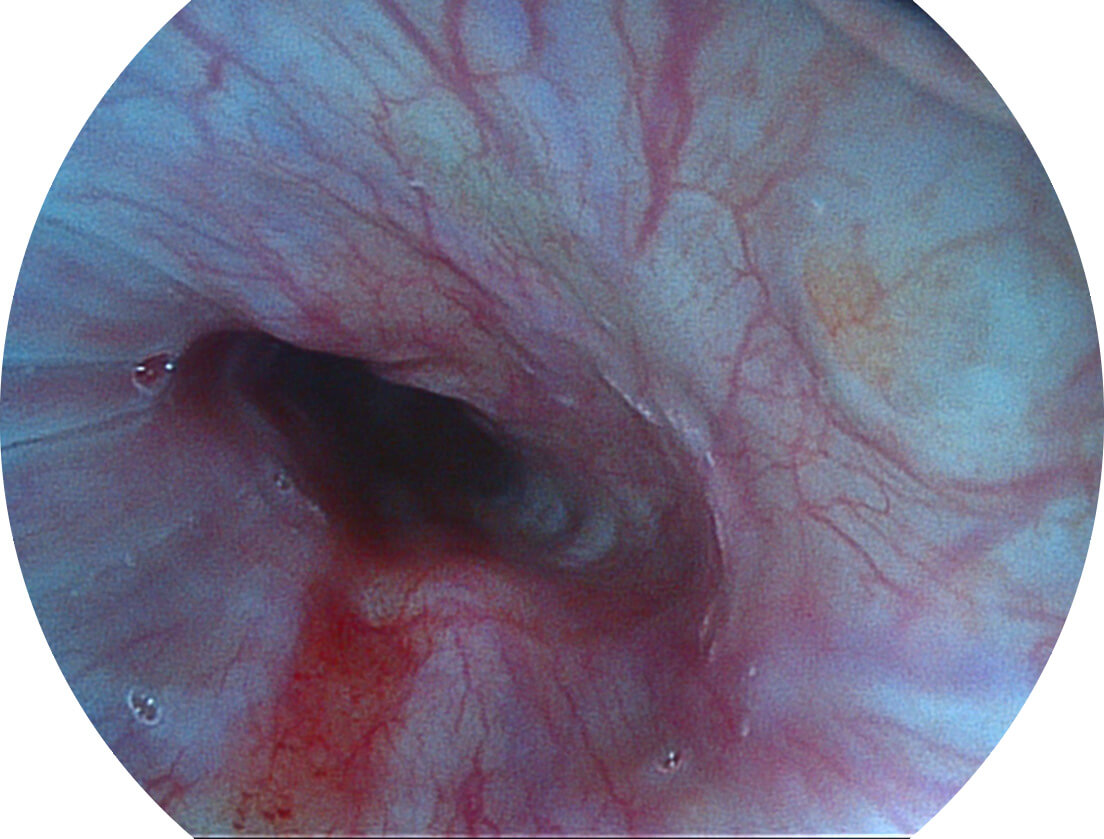

SFI图像

SFI图像

SFI图像

SFI图像

SFI图像

SFI图像

Spectral Focused lmaging, SFI

图像具有高亮度、高黏膜血管颜色对比度的特点,且不改变粘液、食物残渣、粪便的基本颜色,可在中远景下进行观察,助力消化道早期疾病的诊断。